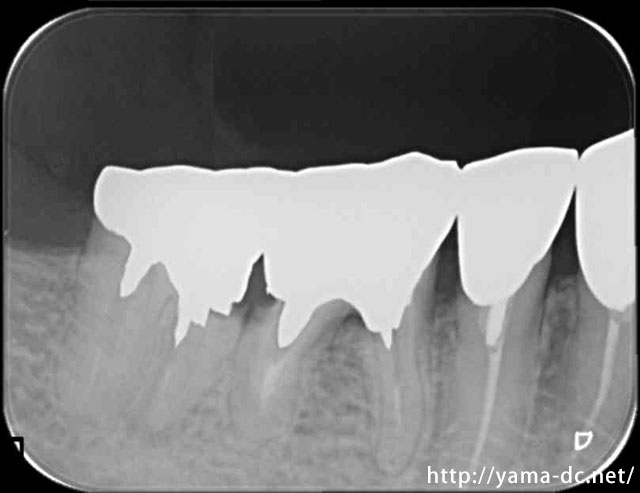

被せ物除去後

歯周外科治療を行う事で歯ぐきと虫歯の治療がきちんと出来ている事が分かると思います。